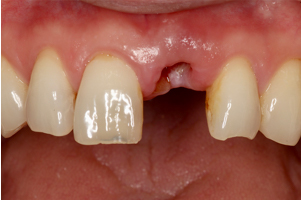

1歯欠損(インプラント1本)

治療前

治療後

歯根破折により、前歯を1本喪失しました。ブリッジ治療と迷われましたが、インプラント治療を選択され、両隣在歯を削らず修復することができました。